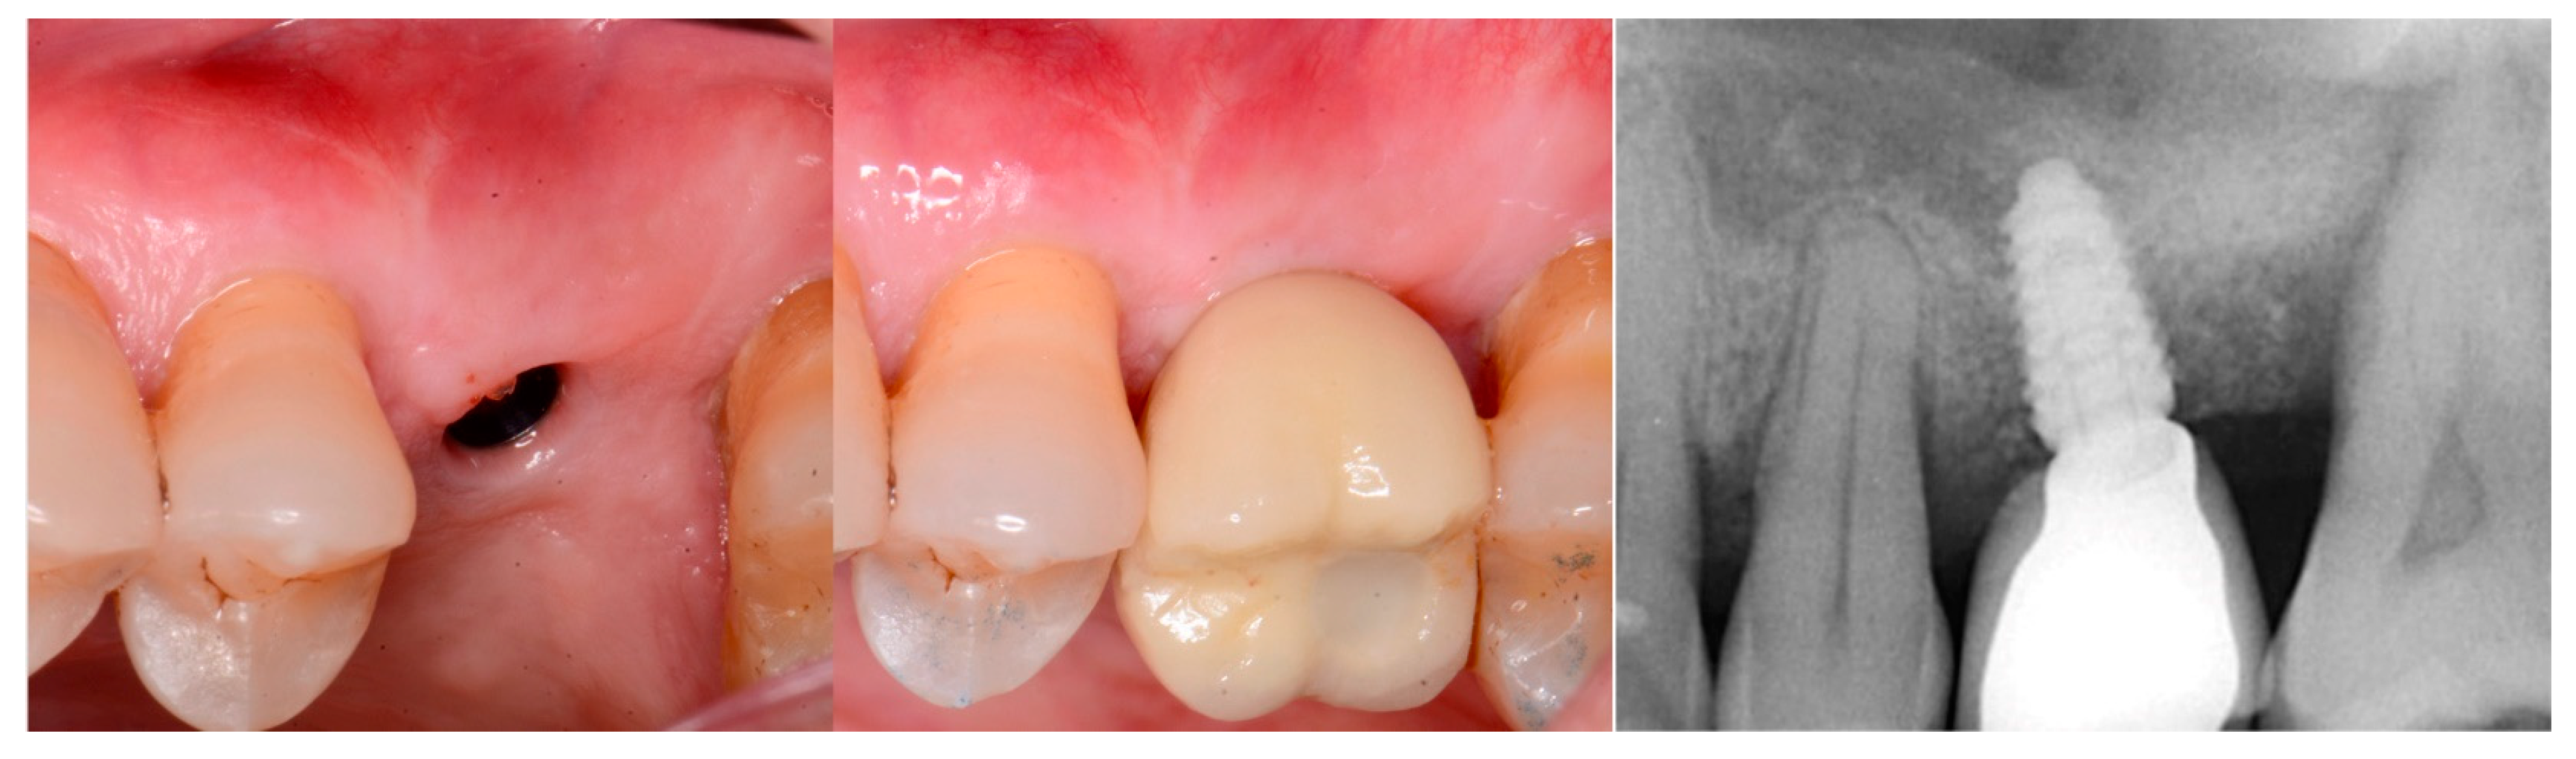

The patient returned at 10 weeks and the implant was uncovered. An impression was obtained, and a healing abutment placed on the site. A radiograph was obtained to verify the healing abutment was seated, which demonstrated conversion of the graft material to immature host bone (Figure 16, right). The restoration was returned from the lab and the patient was returned to complete the treatment. The healing abutment was removed (Figure 17, left) and the restoration was inserted (Figure 17, middle). A radiograph was obtained to verify complete seating of the restoration to the implant (Figure 17, right). Radiographically, the previously grafted area at the crest and sinus blended well with the surrounding host bone.

Figure 16.

Radiograph following crestal sinus augmentation with EthOss and implant placement (left) and at uncovery and healing abutment placement after 10 weeks of implant placement demonstrating conversion of the graft material to host bone (right).

Figure 17.

Healing abutment removal demonstrating noninflamed keratinized tissue over the grafted area (left), placement of the screw retained restoration (middle) and a radiograph to verify mating of the restoration to the implant at the connector (right).